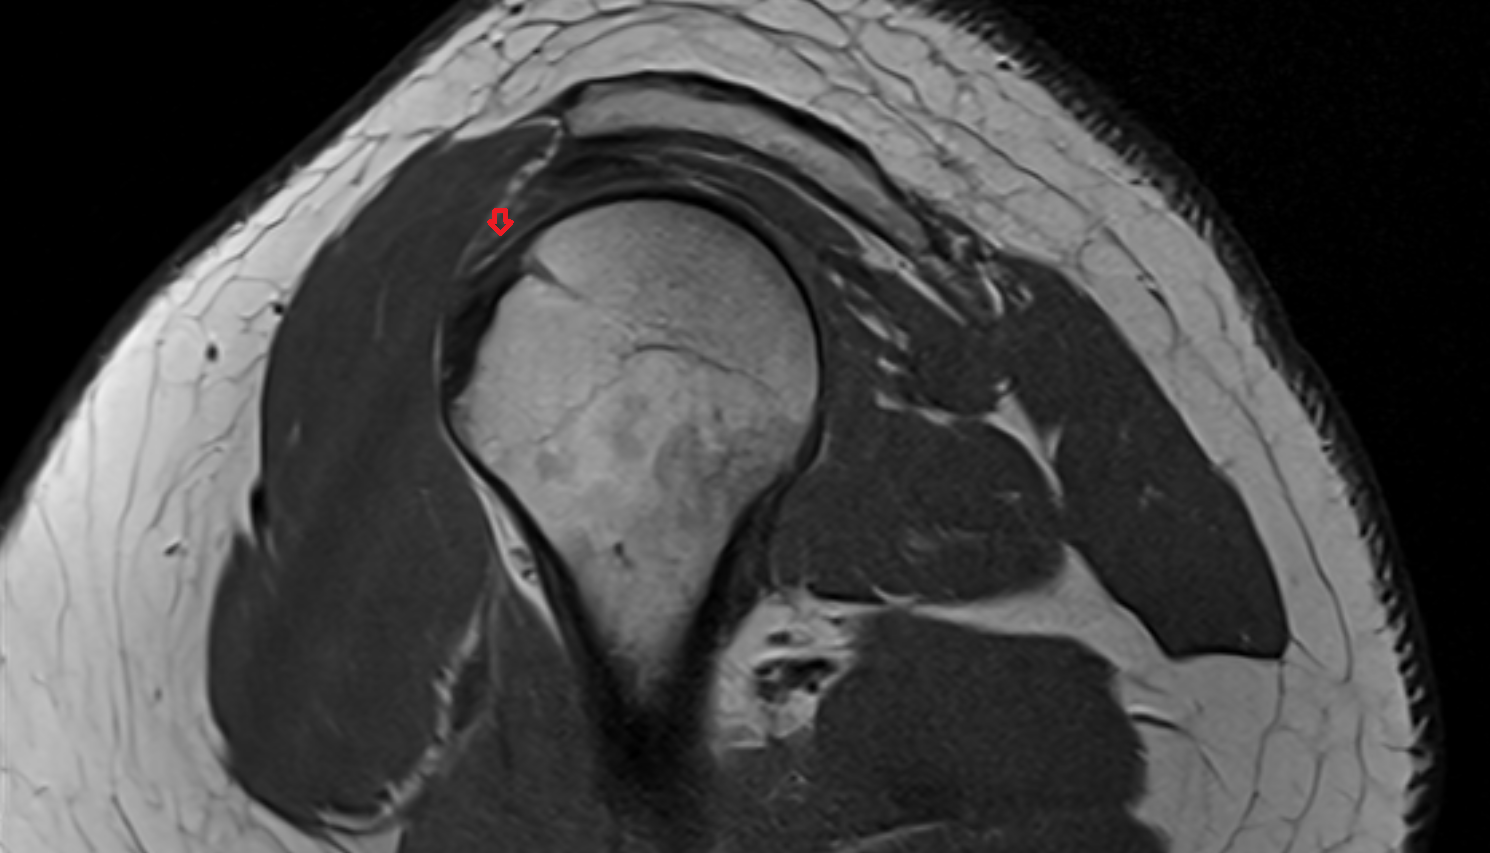

- Supraspinatus tendon

- Shoulder joint (glenohumeral joint)